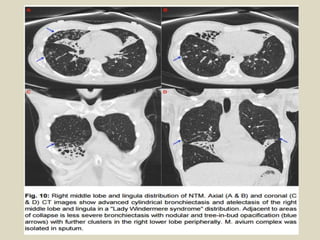

Bronchial Atresia

The most common cause of

congenital focal bronchiectasis

is bronchial atresia,

characterized by obliteration

of a bronchus with distal

bronchiectasis, mucoid

impaction, and air trapping

that is most commonly seen in

the left upper lobe. In this rare

lesion, the bronchial tree

peripheral to the point of

obliteration is patent and the

lung parenchyma is

overinflated because of

collateral air drift.

Bronchial atresia. Transverse image of focal bronchiectasis (arrow) distal to

bronchial atresia associated with hyperlucency and hyperexpansion of left lung.